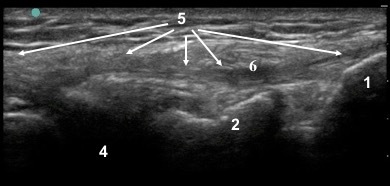

1. Fibular Head

2. Lateral Tibial Condyle

3. Lateral Femoral Epicondyle

4. Lateral Meniscus

5. Lateral Collateral Ligament (LCL)

6. Bicep Femoris Shadow

7. Popliteus Tendon Groove